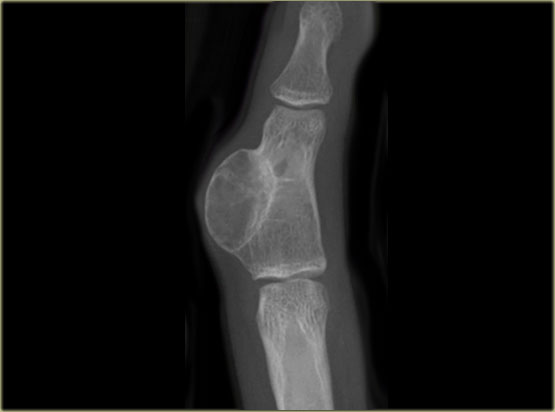

On the left images of a 30-year-old male with well-defined lytic lesion of the olecranon.

On the radiograph several ridges can be seen and a pathologic fracture (arrow).

The T2-weighted image with fat saturation demonstrates fluid-levels due to sedimentation.

Most likely diagnosis: giant cell tumor and ABC.

Biopsy revealed brown tumor.